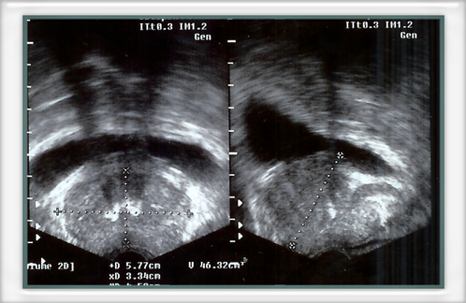

ECOGRAFIA PROSTATICA TRANSRETTALE